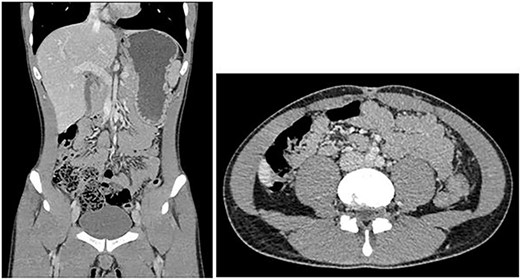

Computed tomography (CT) of the abdomen and pelvis with portal venous phase contrast (see Fig. 1) demonstrated a gas and fluid filled blind structure in the right lower quadrant measuring 40 mm in diameter communicating with a small bowel loop anteriorly. There was a whorled appearance of its neck with subtle surrounding fat stranding suggestive for a torted MD. The appendix appeared to be separate from the abnormality, lying superiorly and to its right with its tip adjacent to the right iliac vessels. Small volume of free fluid in the pelvis was identified without free air in the peritoneal cavity to suggest hollow viscus perforation.

CT abdomen pelvis showing gas and fluid-filled structure in pelvis.